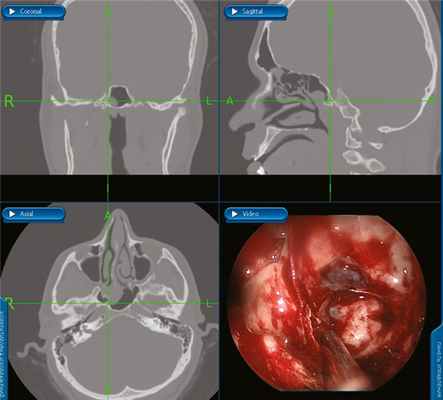

Через 24 ч после эмболизации (15.04.18) под эндотрахеальным наркозом было проведено эндоскопическое удаление опухоли основания черепа с использованием навигационной системы (Medtronic Fusion).

В конце операции было рассверлено место исходного роста опухоли — губчатая кость основания клиновидной кости, видиев канал и крыловидный отросток с правой стороны, мелкие сосуды коагулированы. При помощи навигатора было установлено, что один из сосудов исходил из правой ВСА. При осмотре: опухоль удалена полностью. В полость пазухи введена полоска гемостатического материала Суржицель (рис. 2). Рис. 2. Навигация, окончание операции: навигационный отсос стоит за заднелатеральной границей опухоли, на канале правой ВСА, при эндоскопии видно, что ЮАОЧ удалена радикально, с местом исходного роста. Передняя тампонада носа справа. Интраоперационная кровопотеря составила 2000 мл.